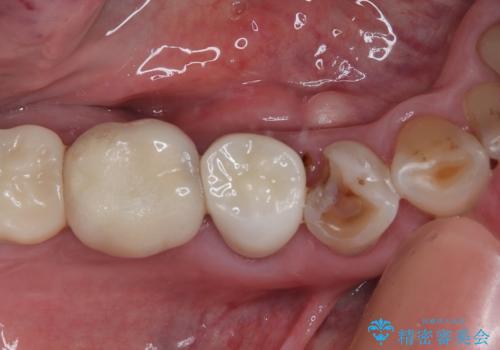

【セラミッククラウン】詰め物と歯の境目に汚れが溜まる

担当医 町田睦月

深い虫歯 セラミッククラウンの精度を高める歯周外科手術